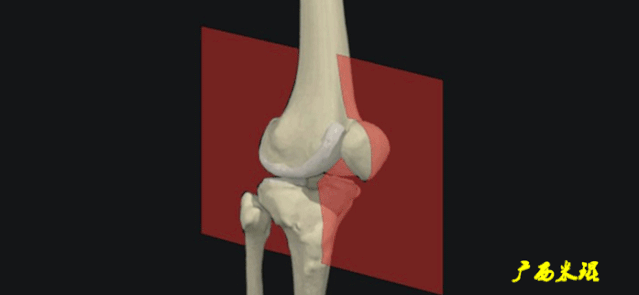

(一)MRI的扫描方向

1.斜矢状面:一般以横断面为定位像,在标准矢状面定位的基础上,将扫描线内旋15°-25°;或以冠状面为定位像,平行于韧带长轴进行扫描。

2.斜冠状面:一般以矢状面为定位像,沿韧带长轴进行扫描。

3.轴状面:扫描层面平行于膝关节间隙。

(四)ACL最好的观察层面

-

最好的观察层面是斜矢状面。

必须结合横断面和冠状面。

(五)ACL角度

矢状面ACL与髁间窝的顶部形成一个13°的夹角。